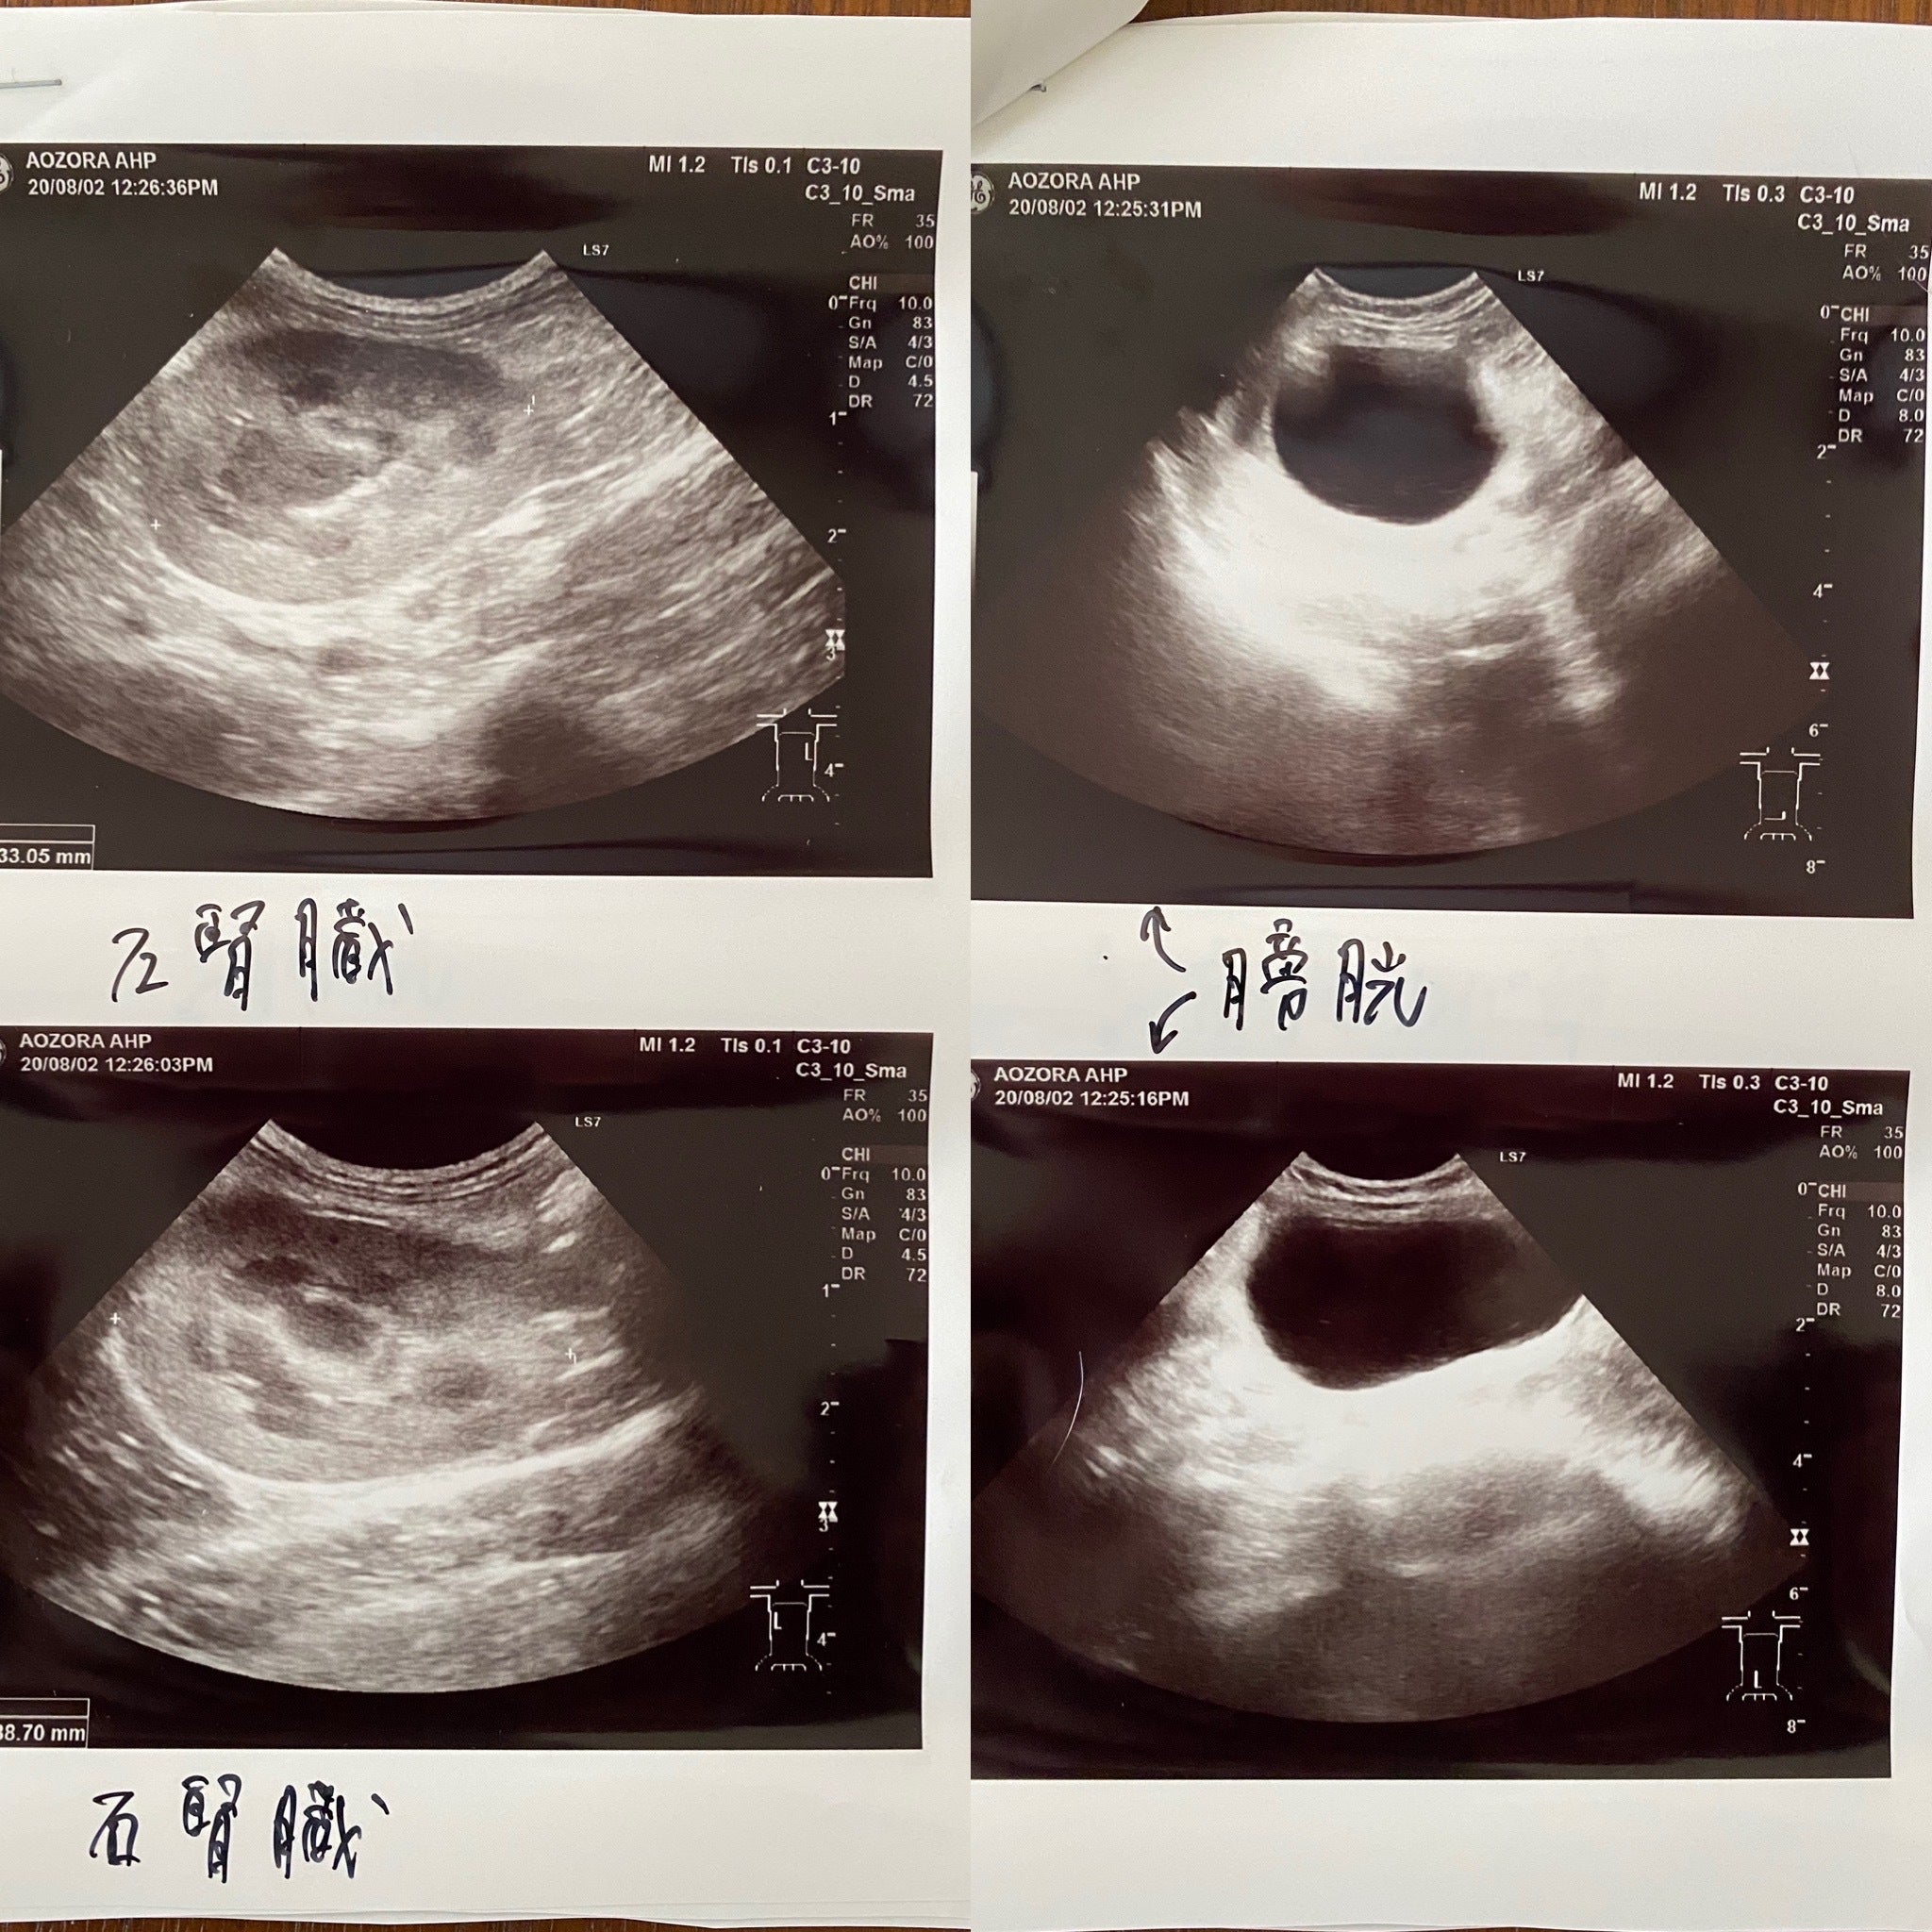

検査入院中のテオ

実は7年前に生後5ヶ月の子猫をこのFIPで亡くし非常に辛い思いをしました。そして今回のテオです。何とか治療を受けさせ治してあげたいと思い、色々と調べました。なんと偶然にも同じ市内にこのサプリメントの協力病院があるのを知りました。すぐに病院に電話し診察をして頂きました。結果はFIP混合型でした(FIPには3種類あり①ウエットタイプ②ドライタイプそして①②の混合型があります)。そして黄疸も出ており肝臓も良くないとの事でした。